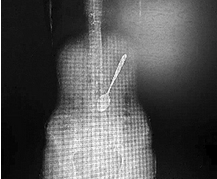

ابتلعت سيدة صينية 27 عاما ، ملعقة معدنية أثناء تناولها طبق معكرونة في مقاطعة "جيانجسو" الصينية ، فهرعت السيدة على إثر الحادثة إلى المشفى لإخراج الملعقة حتى لا تتسبب بأي مشاكل صحية إذا بقيت فترة طويلة.

ومكثت الملعقة في بطنها 3 ساعات قبل أن يتمكن الأطباء من تنفيذ مهمتهم باستخدام أدوات طبية دقيقة ، متجنبين حدوث أي تلف في معدة المريضة.